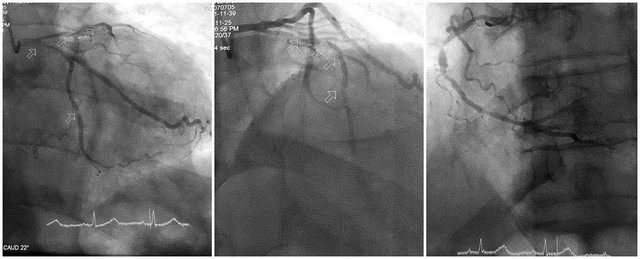

Kết quả chụp mạch vành cho thấy mức độ tổn thương đặc biệt nghiêm trọng: Động mạch liên thất trước hẹp tới 90–99%, gần như tắc hoàn toàn; động mạch mũ và động mạch vành phải hẹp 80–90%; hệ mạch vành vôi hóa nặng, thành mạch cứng, làm tăng nguy cơ biến chứng khi can thiệp.

Ảnh: BVCC